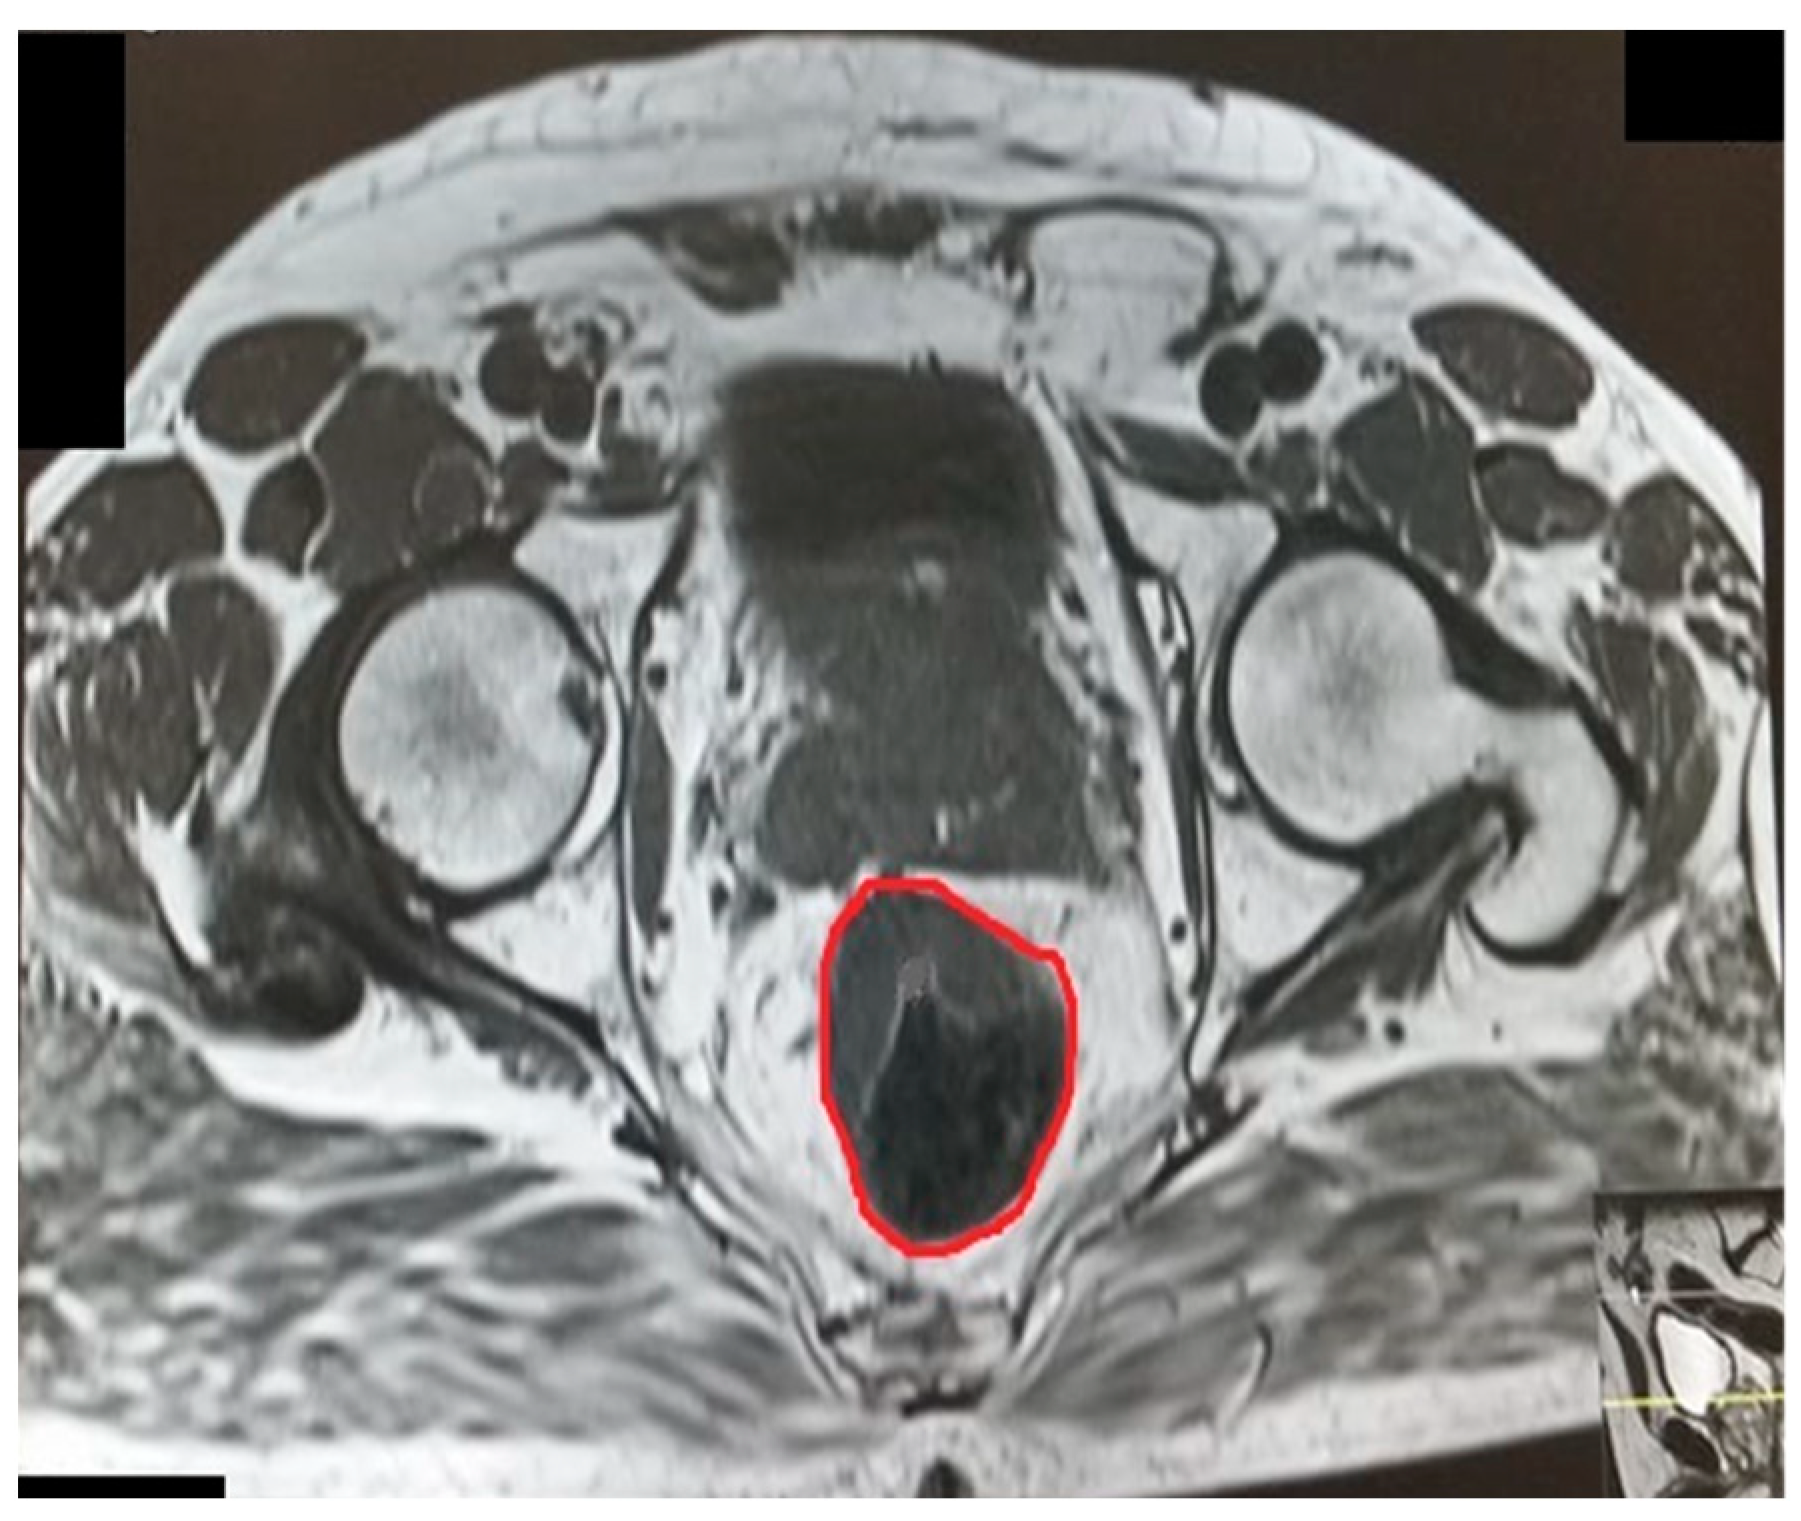

The pelvic measurements on MRI (Figure 2, Figure 3, Figure 4, Figure 5, Figure 6 and Figure 7) were carried out by the author, and to maintain the reproducibility of the results, measurements were taken, whenever possible, at the same anatomical levels.

Figure 6.

Rectal area.

Figure 7.

Mesorectal area.